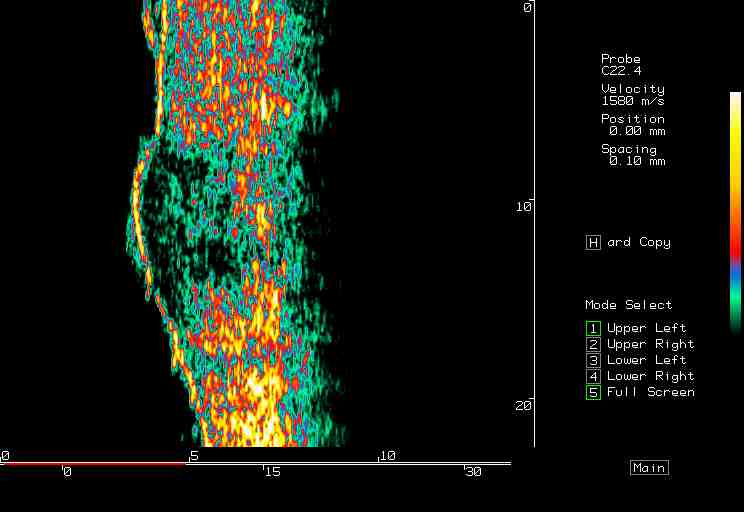

20 MHz 2D images

| Cellulite |  Cellulite 1, thigh |

Cellulite2, thigh |

Cellulite 3, thigh |